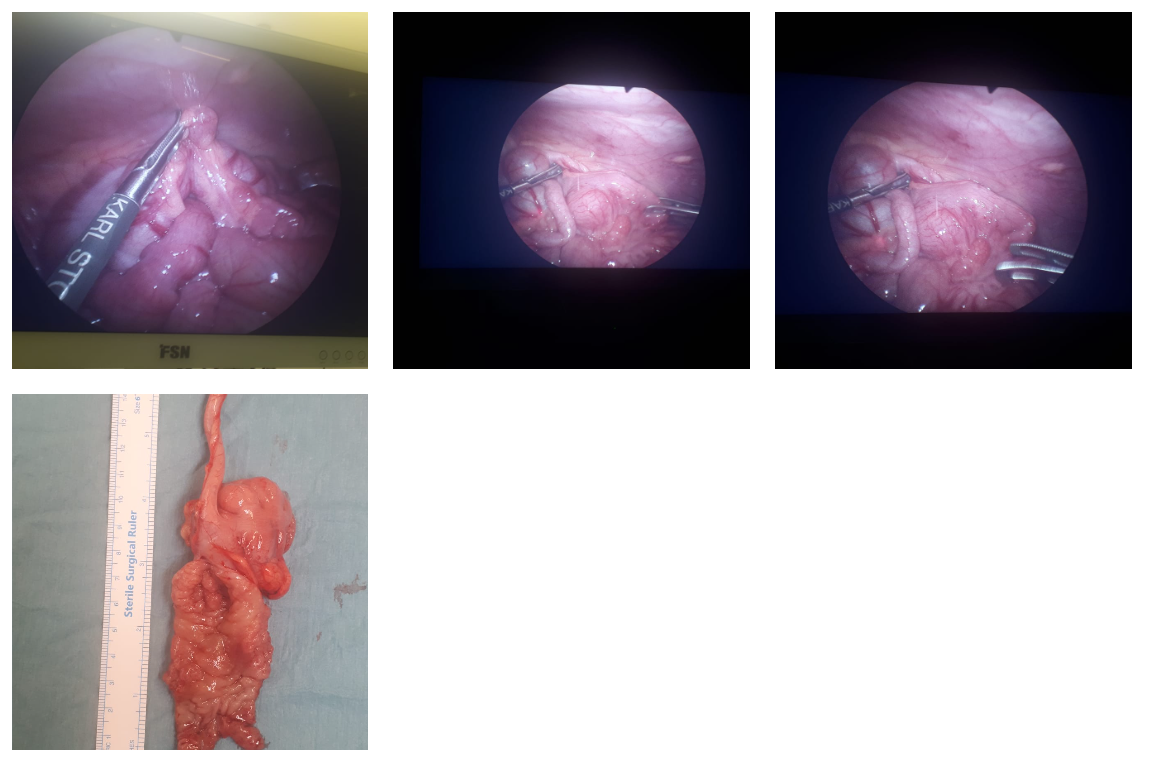

One stage Trans-anal Swenson’s Pullthrough was performed for Hirschsprung Disease in a 3 months old girl child. This child had presented with life threatening enterocolitis when she was diagnosed with Hirschsprung’s disease affecting Rectum, distal half of sigmoid colon. After intense bowel management , she underwent complete trans anal mobilization of rectum and colon upto mid sigmoid and with Frozen section guidance normal ganglionic segment was identified and excision of aganglionic segment with coloanal anastomosis was performed. Typically this procedure is done in stages with colostomy and laparotomy/laparoscopy which requires multiple surgeries, anaesthesia s and leaves a large scar. Child required minimal analgesia,could be fed few hours after surgery and passed stool spontaneously , discharged in 2 days post op.

There is no scar on her abdomen or perineum which is a great cosmetic benefit to the girl child.